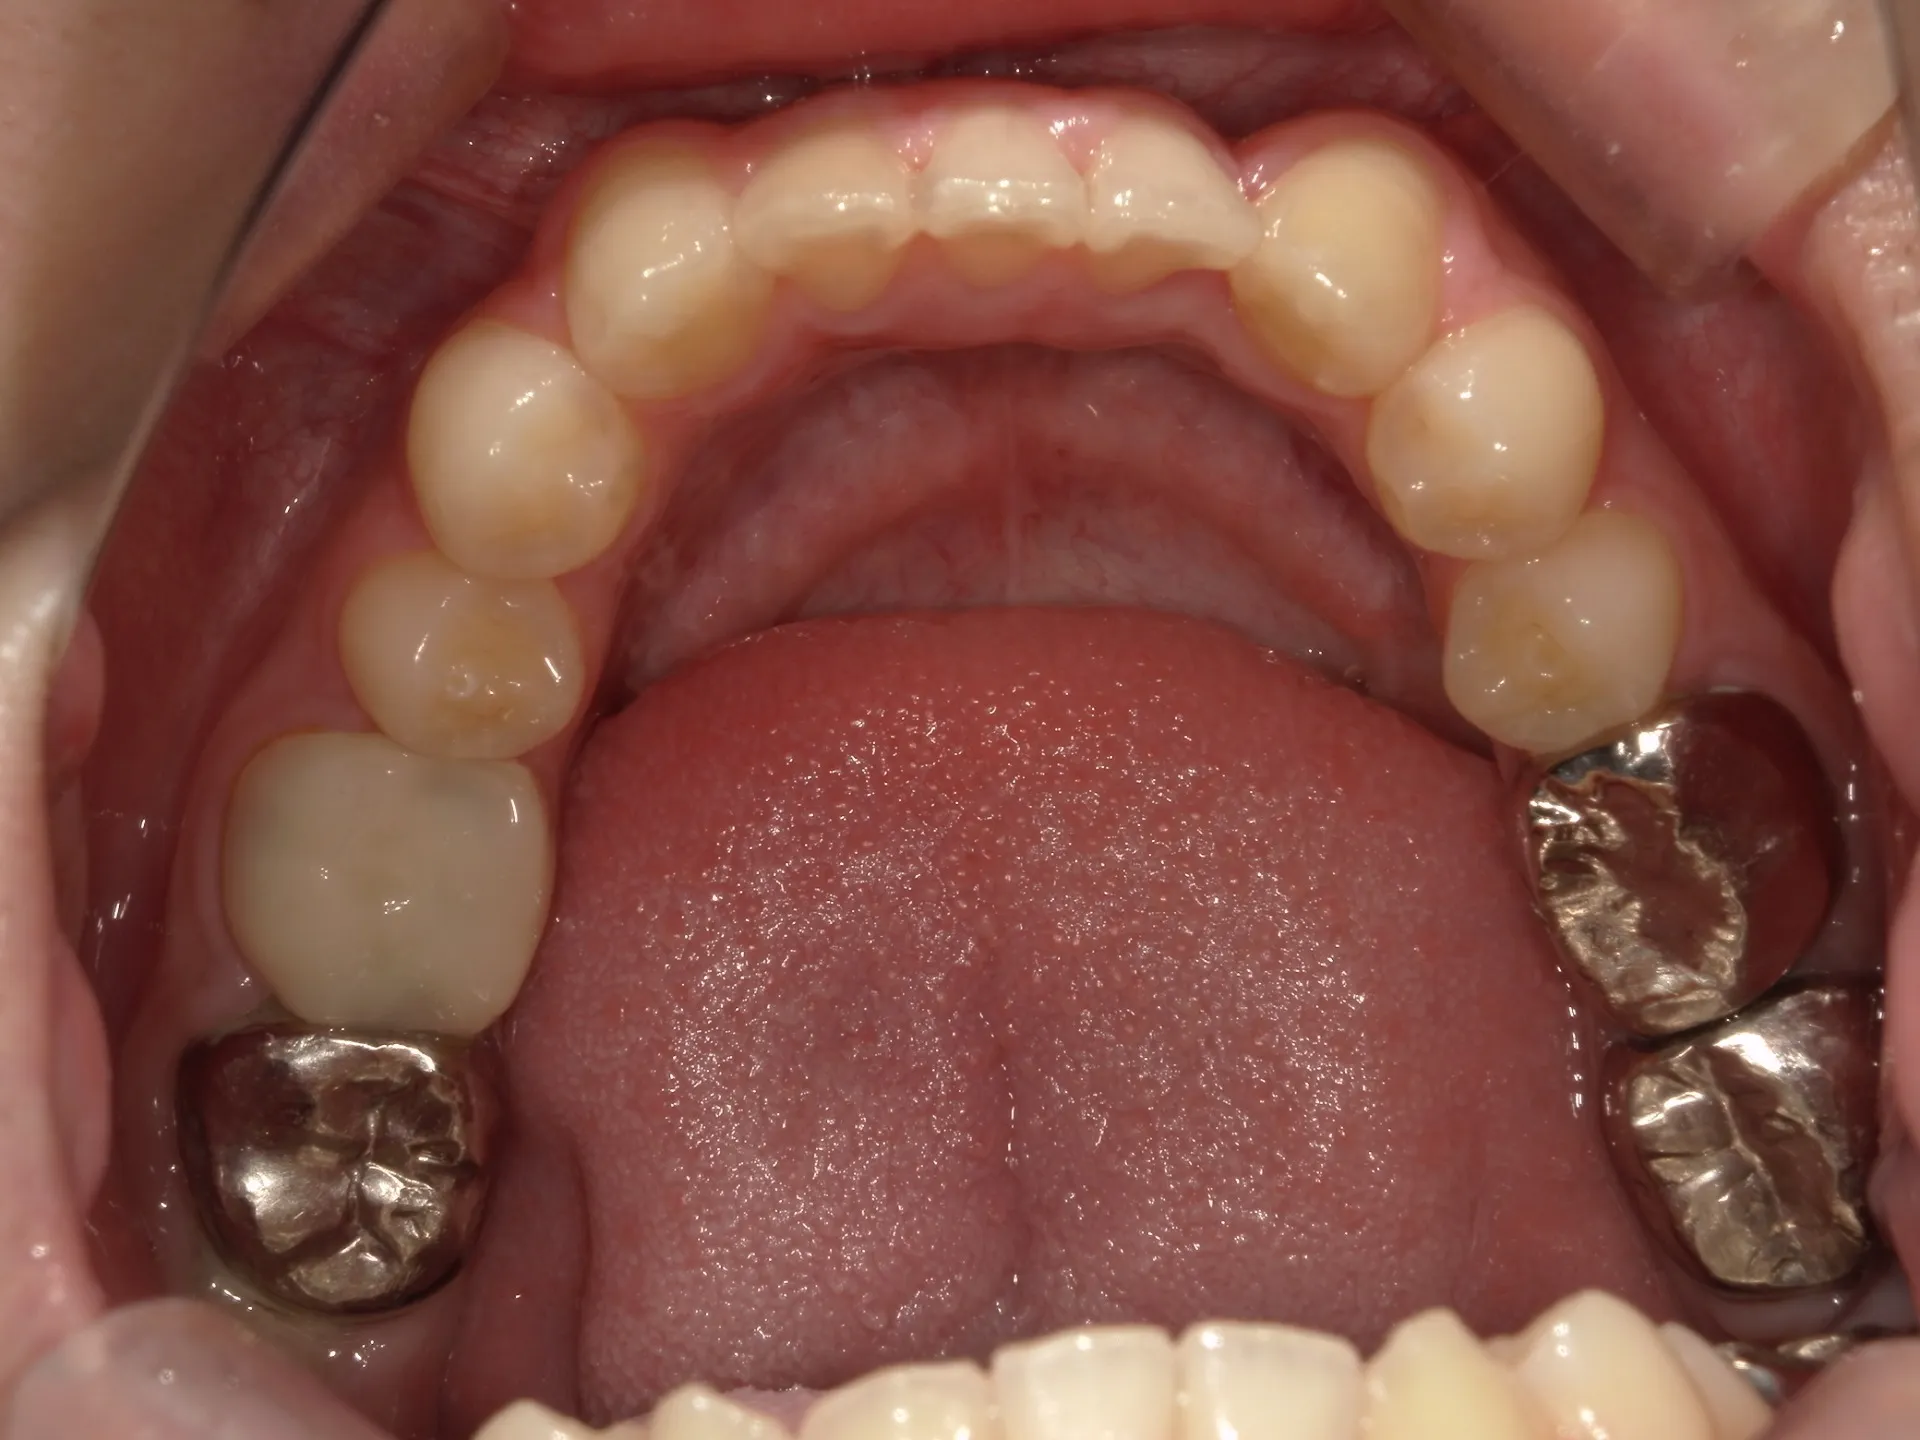

今回は下の前歯が1本ない場合の矯正治療についてご紹介いたします。